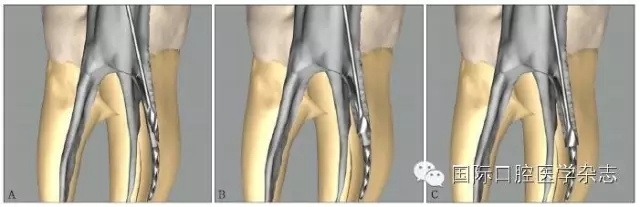

3.2.5 取出難度評估 多數(shù)情況下,如果分離器械上1/3能夠暴露,通常能夠取出。位于直根管、近根管口的分離器械較位于彎曲根管的器械容易取出。位于根管通暢部分的分離器械通??梢匀〕?。如果分離器械位于根管彎曲附近,并且牙本質(zhì)厚度容許建立從根管口到器械冠方的通道以接近其冠部末端,而不至于產(chǎn)生穿孔等并發(fā)癥,則仍有可能將其取出。在這些病例中,都必須建立到達(dá)分離器械上部的直線通路。如果器械分離于彎曲根管的根尖部,則很難建立安全的通道,且分離器械移動(dòng)可能造成器械超出根尖孔,風(fēng)險(xiǎn)較大,通常不太可能將其去除(圖8)。

A:分離器械位于較直的根管中上部分,較容易取出;B~D:分離器械位于根管彎曲之下或彎曲根管近根尖部,無法取出。

圖 8 取出難度的評估